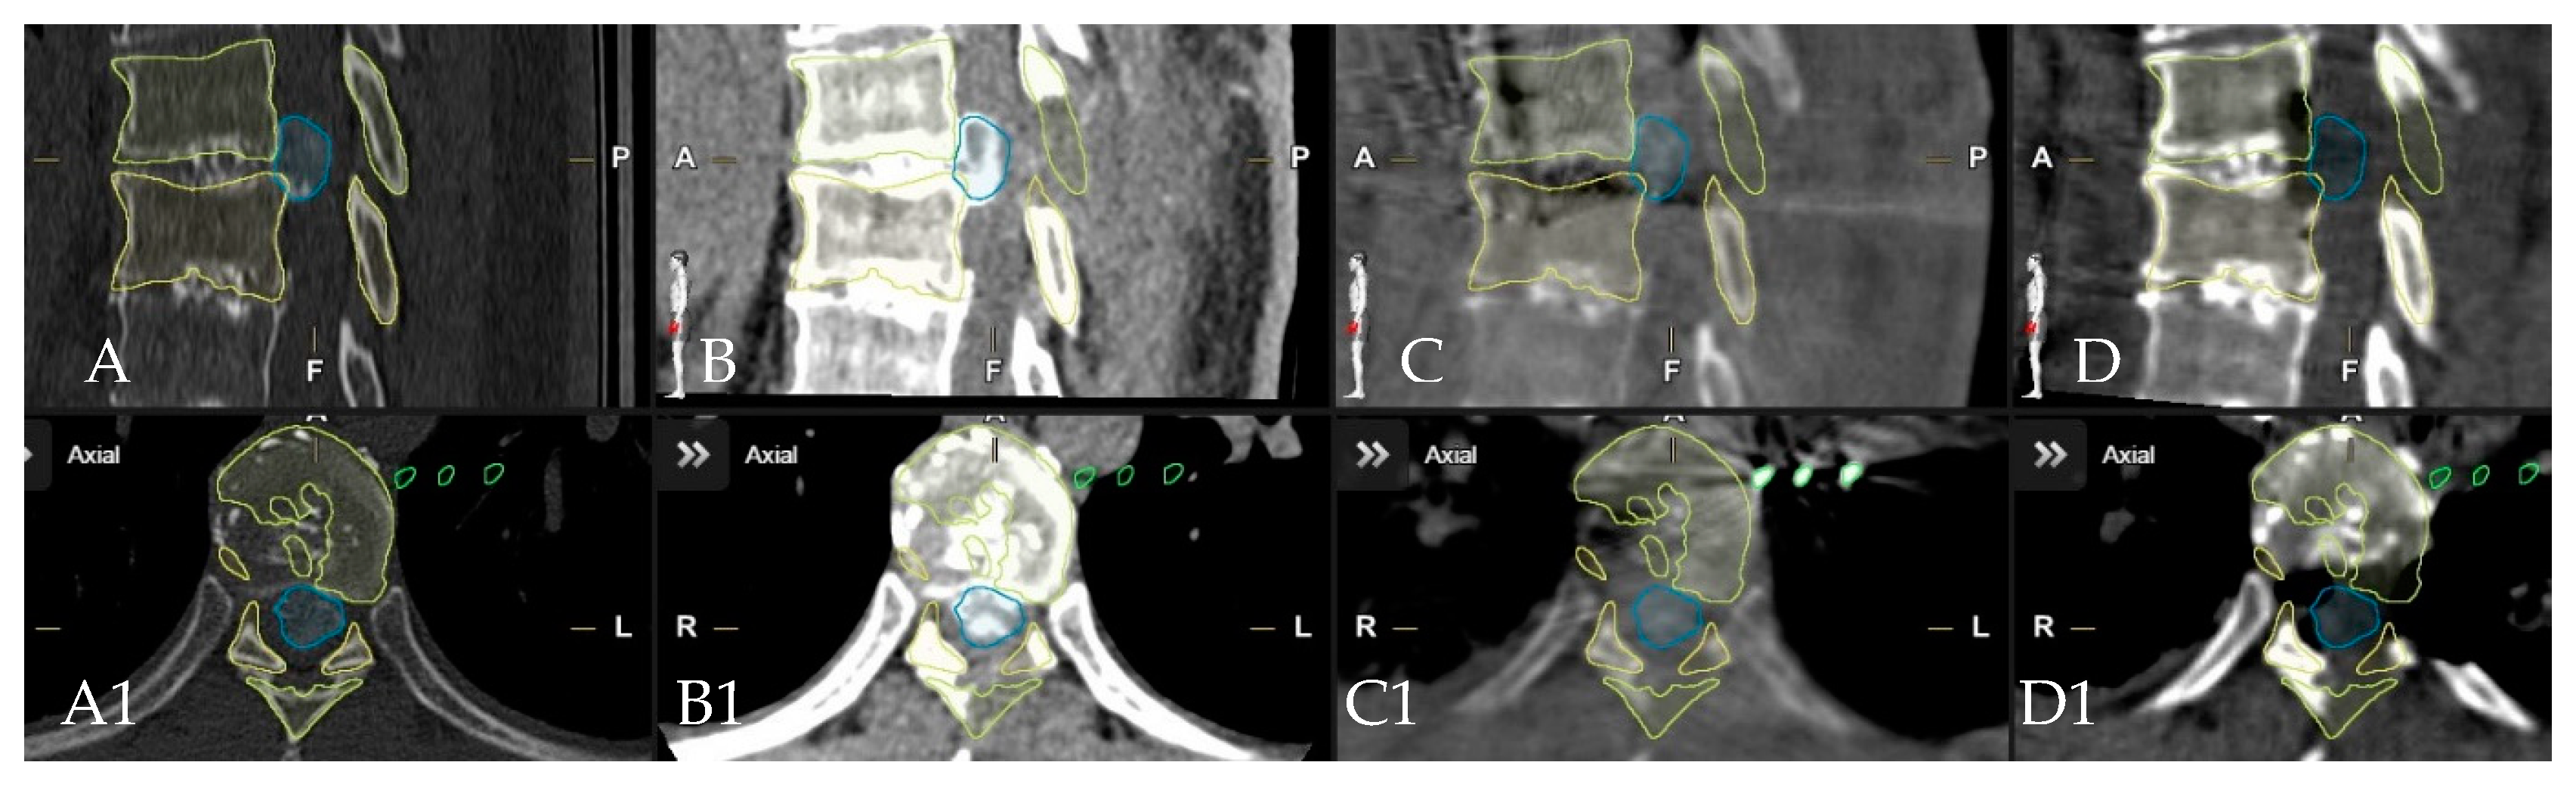

4. Patients